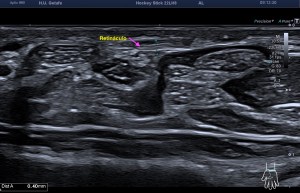

La radiografía revela aumento de las partes y se refrenda en la ecografía como puedes ver en la imagen aunque aún no hay afectación en el hueso en el caso que te presento hoy.

Ecografícamente y debido a su levedad, en el caso de hoy solo observamos cambios en las partes blandas de la cara lateral de la cabeza del quinto metatarsiano, este tejido se muestra heterogéneo, la cortical del hueso ligeramente prominente sin afectación de la misma.